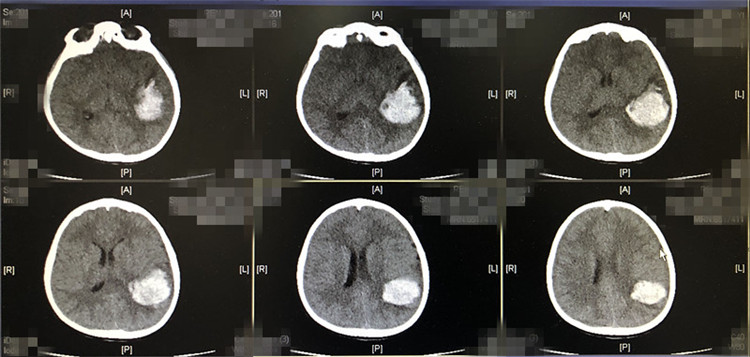

通过CT照片检查,确定小涛颅内约有50-60毫升的出血,导致颅内高压,必须立即手术清除血肿,否则大出血形成脑疝,将造成呼吸衰竭导致死亡。

通过迅速的术前准备,下午两点,小涛被推进手术室。历时3个小时,医生成功将小涛左侧颞顶叶脑内血肿清除干净。术后小涛被送进重症监护室,当天顺利脱离呼吸机。在医护人员的救治下,小涛已于昨(23)日顺利出院。